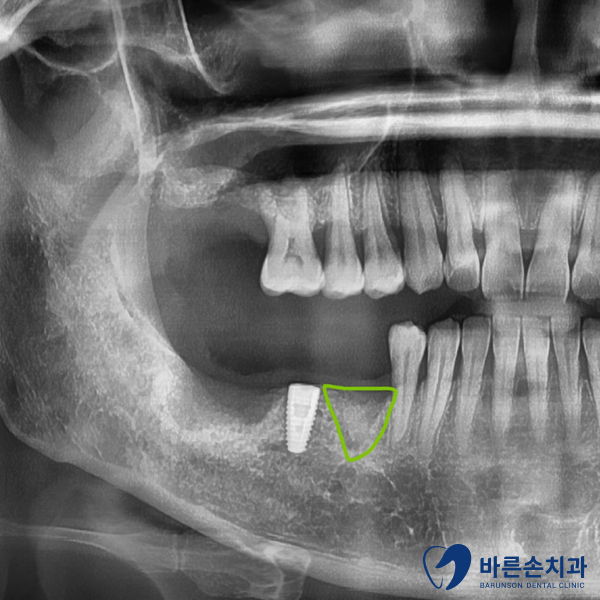

임플란트 식립을 진행하고 2개월 정도 더 기다렸다가

치아머리 부분 보철물을 제작했습니다.

(스트라우만 임플란트는, 치조골과의 결합력이 월등히 좋기 때문에,

치료 기간을 앞당길수 있습니다.)

이렇게 임플란트 수술이 성공적으로 끝나게 되었습니다!

임플란트 주위 뼈도 단단하게 잘 형성되어 있습니다.